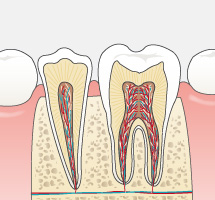

今まで一般的に行われていたむし歯治療は、痛くなったら歯医者に行き治療する、という流れの繰り返しではなかったでしょうか?痛くなってから、むし歯が進行してからの治療は削る・抜歯することが多くなり、徐々に自分自身の天然の歯は「詰め物」や「被せ物」さらには「インプラント」や「入れ歯」になっていきます。天然歯は削ってしまうと二度と元には戻りません。

可能な限りご自身の歯で食事を楽しんだり、話したりして健康な生活を送っていただきたい。だからこそ当院ではできるだけ歯を残す治療をおこないます。単なる対症療法の“削って詰める”ではなく、病原菌の除去をしてからMI(Minimal Intervention:できるかぎり削らず、削っても最小の範囲で)の考えのもと原因療法を施し、治療後はむし歯の再発や新たなむし歯の発生を予防することを目標としています。